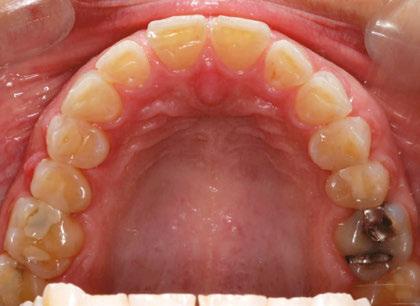

Figures 7-10: Images with braces, with and without coils, facial and maxillary occlusal views